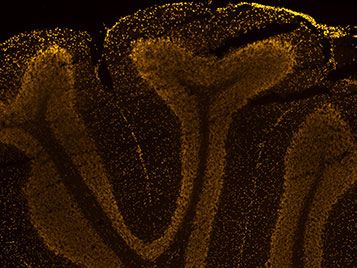

View of the Cerebellum

Here you can see a cross-section of the cerebellum, which plays an important role in controlling movement. The light-colored structures resemble pistils and contain Purkinje cells, named after their discoverer, and granule cells. Purkinje cells were first observed in 1837 and formed the basis of the Neuron doctrine They are located in a feedback loop between the brain's movement commands and the actual change in posture, which is communicated via the Spinal cord For more information and exciting images on this topic, see our slideshow ▸ Communication under the microscope.